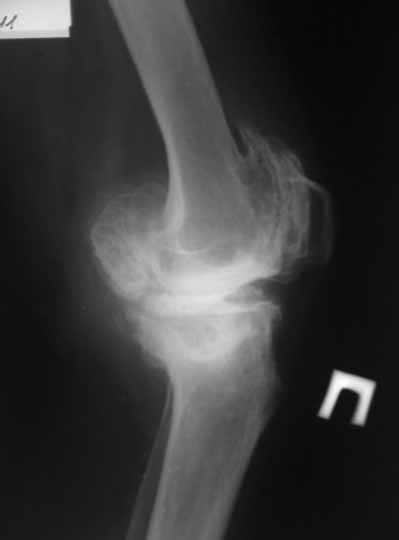

Пациентка 72 лет.Не обследовалась и не лечилась.

Работала поварихой до последнего времени.обратилась за медпомощью впервые.ходит без дополнительной опоры. Основные жалобы на ограничение движений и боли в правом коленном суставе.

Финансовые возможности ограничены.Чем можно помочь? Артродез? Протезирование?

Здравствуйте! А у вас нет ли R-гр? Для установления ст. артроза. Если же пациентка обращается первично, может стоит попробовать консервативное лечение?! НПВП, физиолечение, массаж, внутрисуставные блокады... Артродез и протезирование думаю всегда успеется.

однозначно протезирование

Anatoly Yakushin 08 Апрель 2011, 05:58

Больной несомненно показано эндопротезирование, однако случай не простой. Если у Вас нет достаточного опыта в проведении подобных операций, лучше направить больную в соответствующее лечебное

учреждение. По квоте.